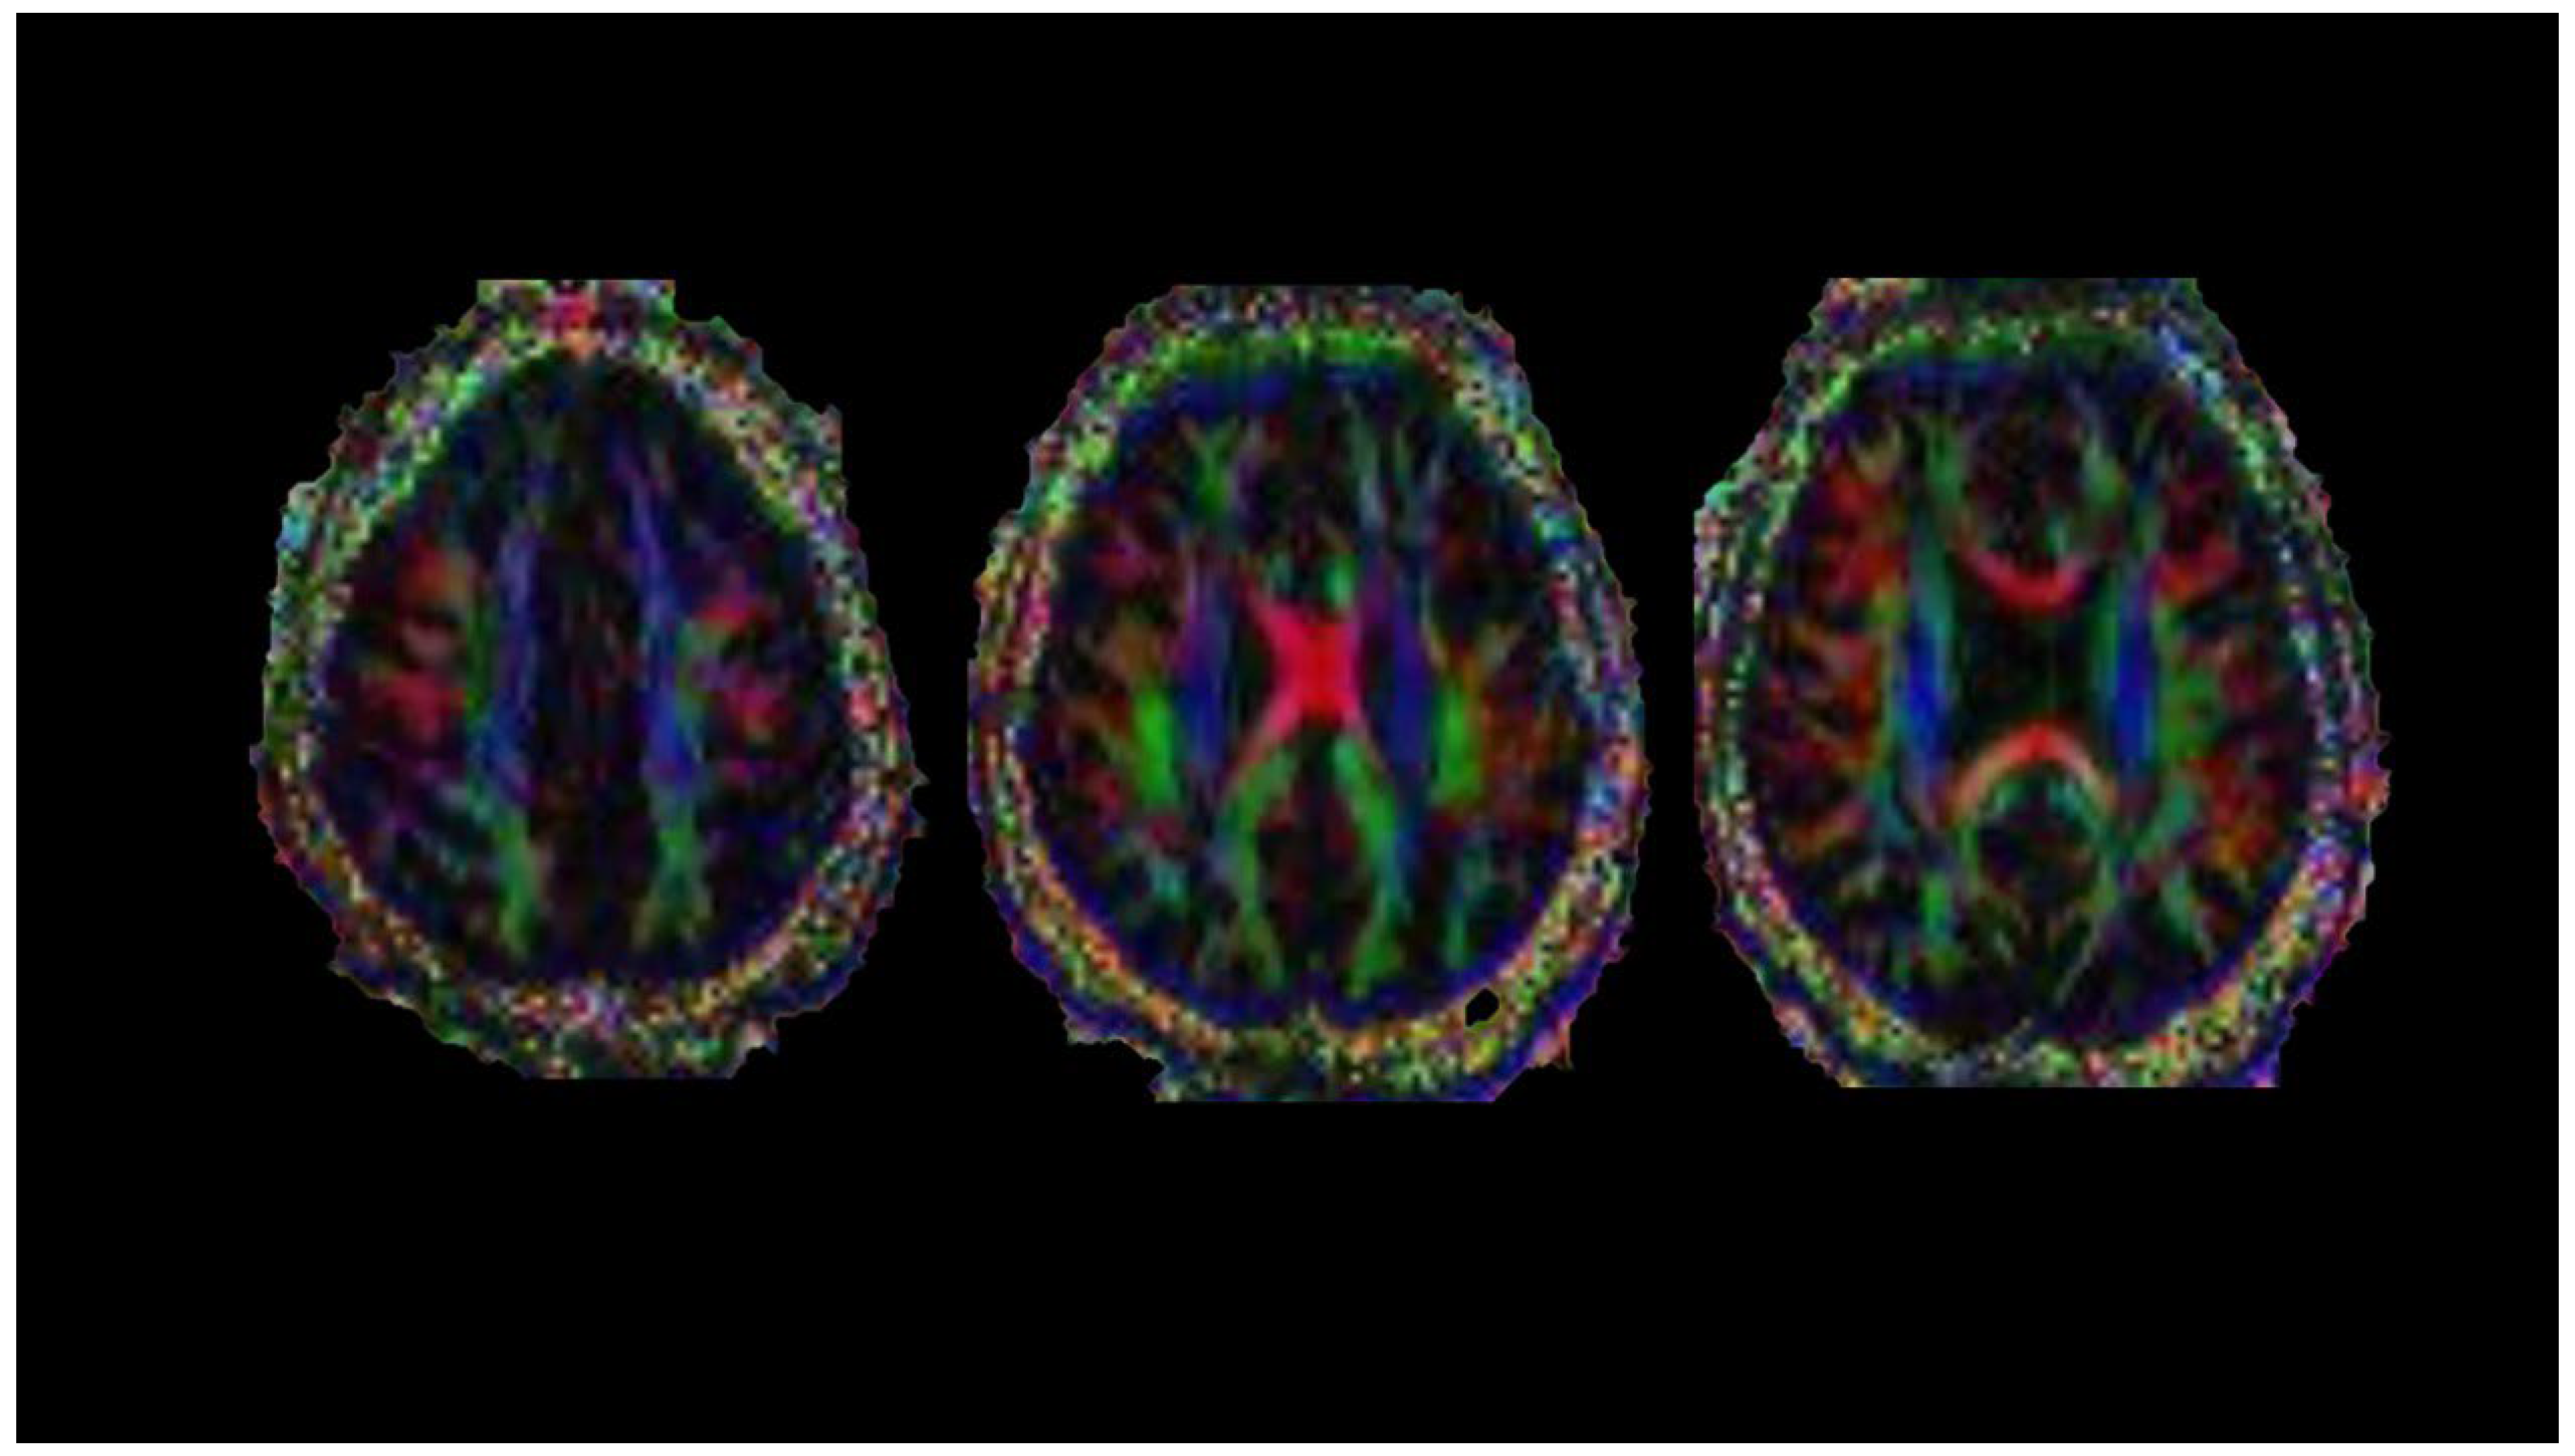

8. Diffusion Tensor Imaging

| DTI | Pre-lesion alteration in NAWM | Early detection of new lesions | Lack of specificity |